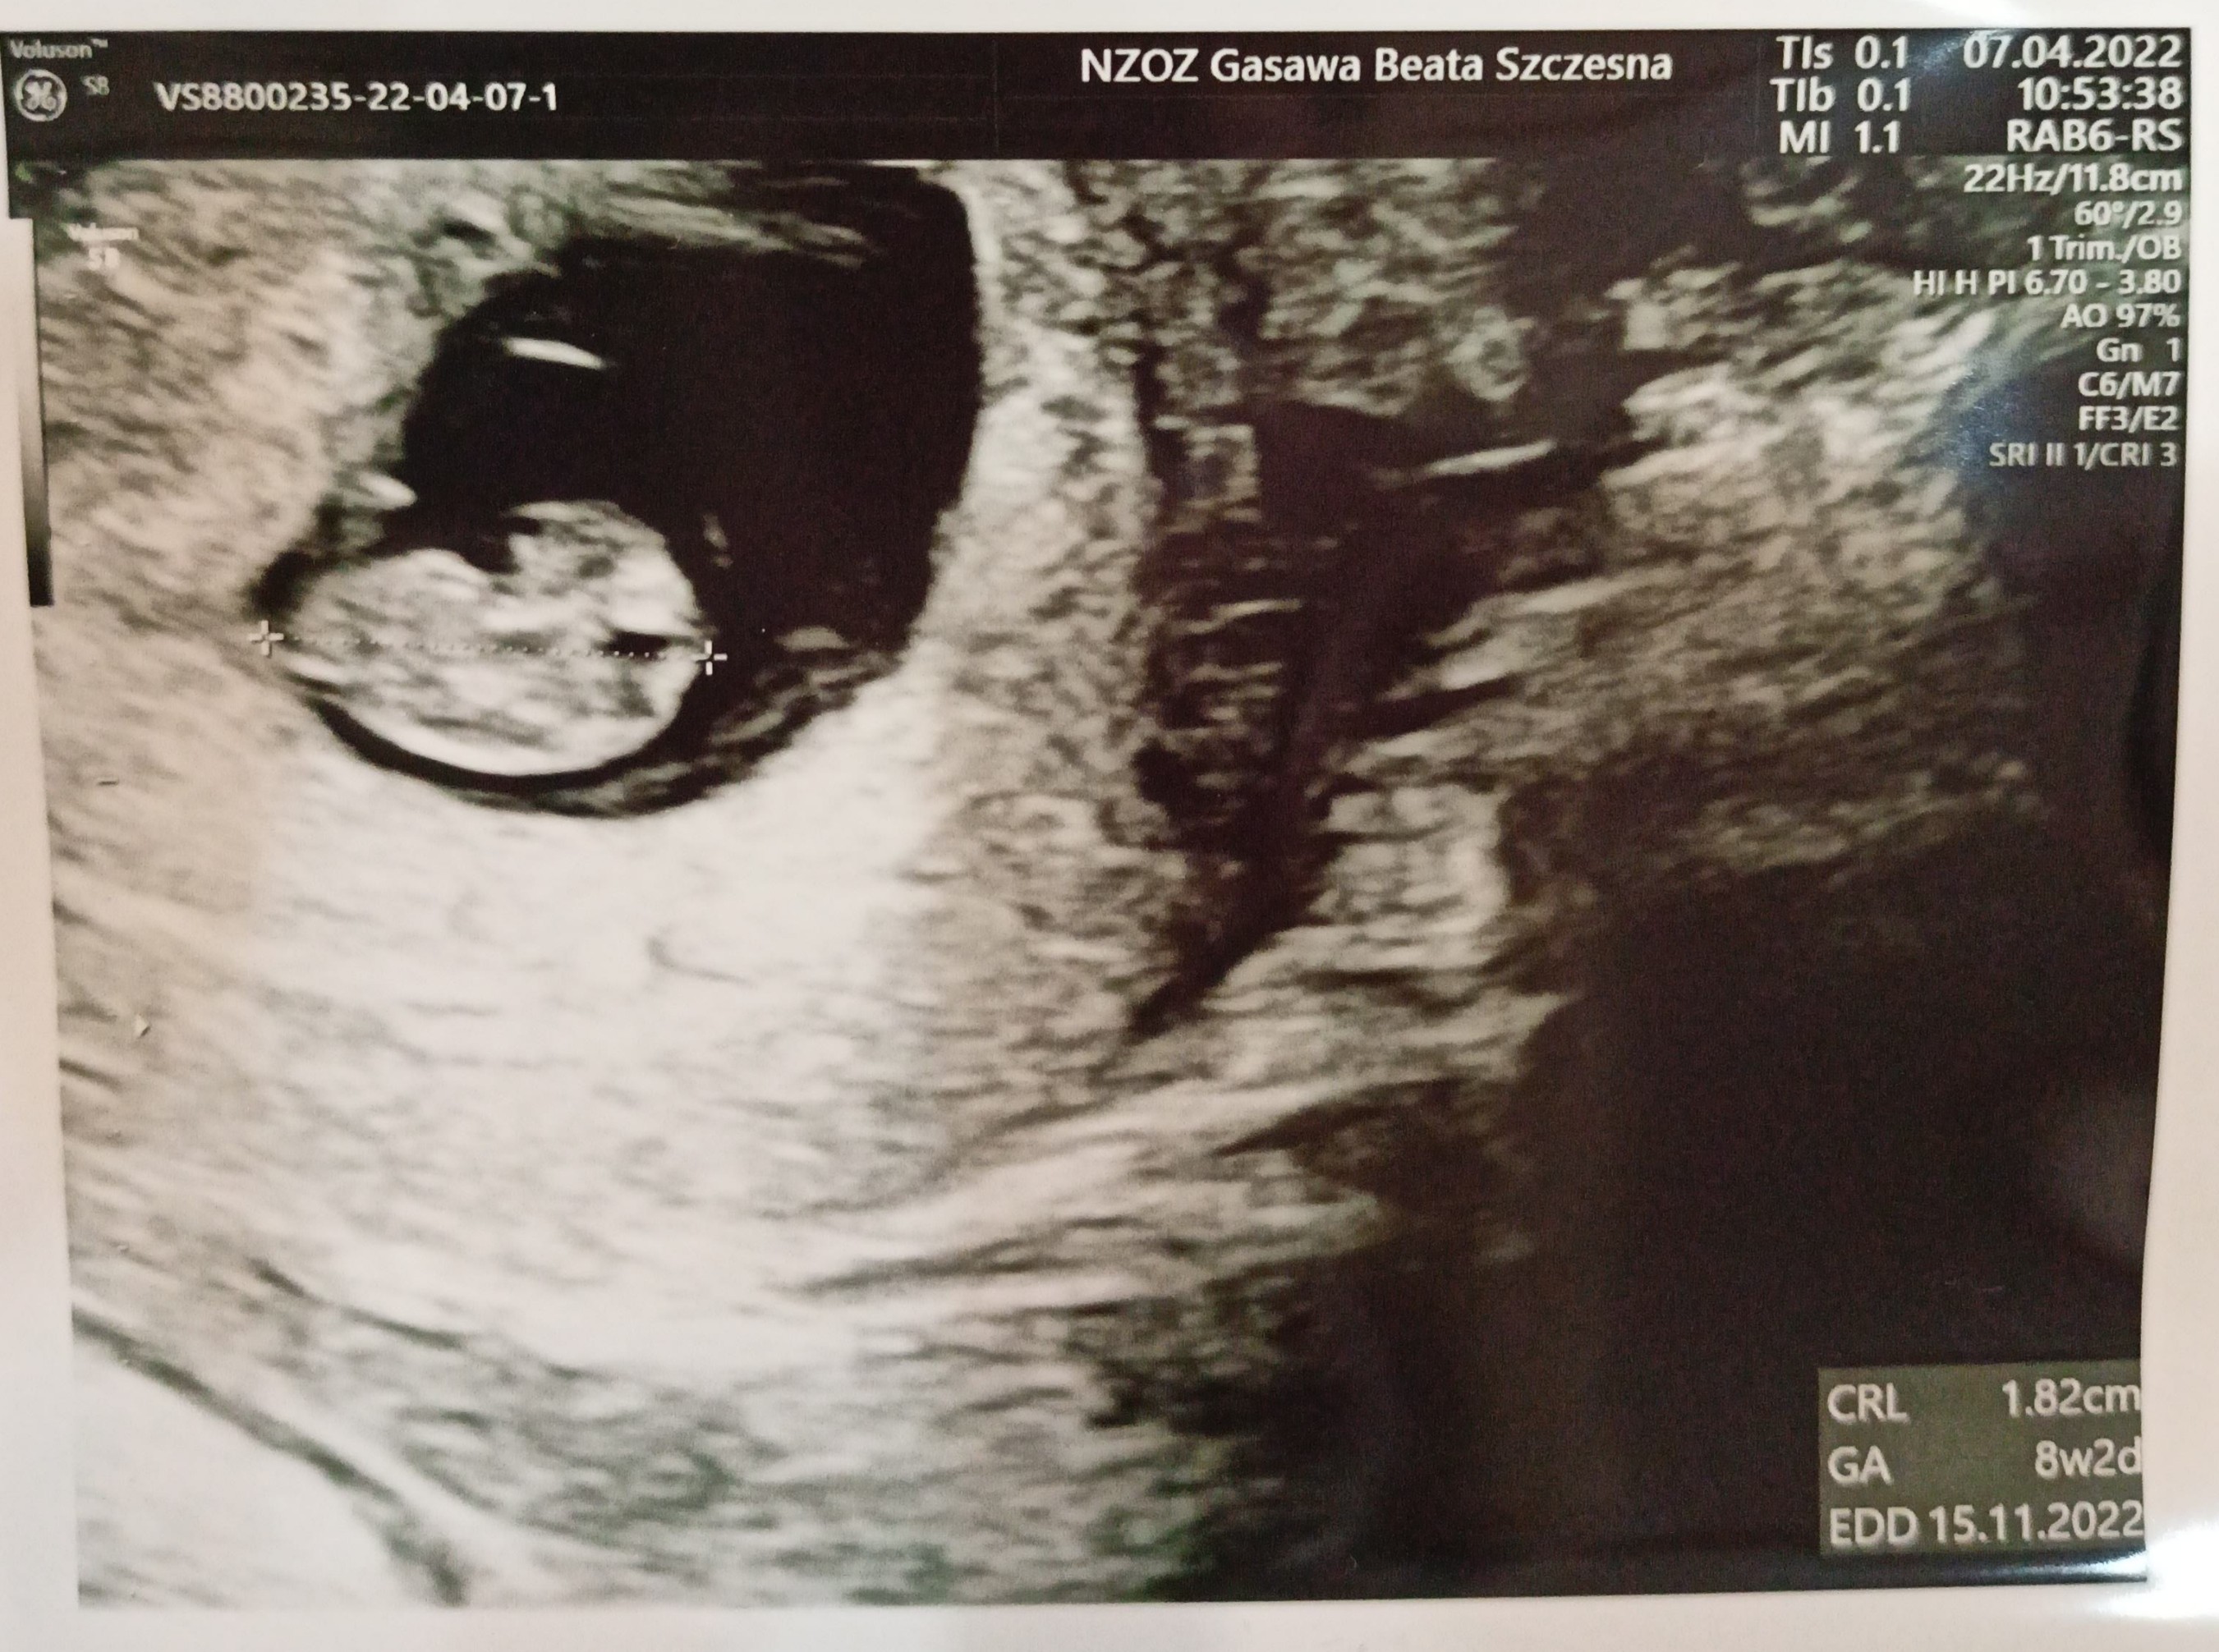

Jestem już po wizycie, póki co wszystko w porządku. Bąbel ma 1,82cm, serduszko szybko mu bije, mózg jest, płyny mózgowo rdzeniowe w porządku. Za dwa tygodnie kolejna wizyta i wtedy założymy kartę ciąży, lekarz mówi że zakłada jak ma 100% pewności że się dobrze rozwija, a ja poroniłam ostatnio w tych okolicach 8 tygodnia więc zaczekamy. Niby się cieszę ale dalej się boje 🙈 babie nie dogodzisz 🤣

Termin z USG zrównał się z tym z miesiączki, więc to chyba dobrze, bobo nadgonilo 😁 Zobacz załącznik 1387504